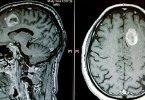

• 脑垂体腺瘤的治疗方法

脑垂体腺瘤的治疗方法

脑垂体腺瘤的治疗方法主要有药物治疗、手术治疗、放射治疗、定期观察随访以及生活方式调整。脑垂体腺瘤的治疗需根据肿瘤类型、大小、激素分泌情况及患者个体差异综合制定方案。1、药物治疗适用于分泌型垂体腺瘤或术 ...